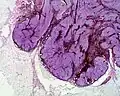

Cellular blue nevus

Cellular blue nevus -